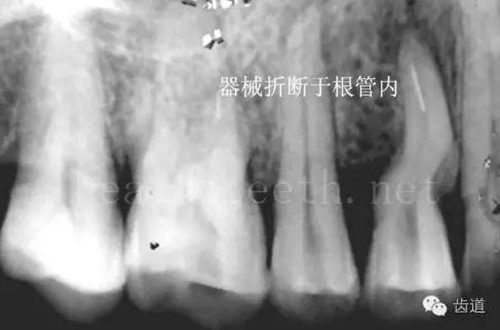

不良的根管充填治療

77.jpg